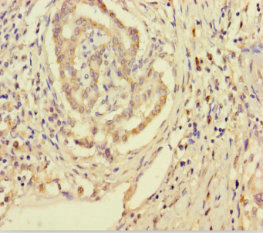

Immunohistochemistry of paraffin-embedded human pancreatic cancer using CSB-PA878920LA01HU at dilution of 1:100